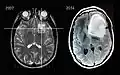

1. Astrocitoma de bajo grado del mesencéfalo (lámina tecti), resonancia magnética sagital ponderada en T1 después de la administración de medio de contraste: el tumor está marcado con una flecha. Los espacios del LCR frente al tumor se expanden debido a la hidrocefalia interna inducida por compresión.. -

Imágenes por resonancia magnética de un paciente con astrocitoma, que muestran la progresión del tumor en el transcurso de siete años